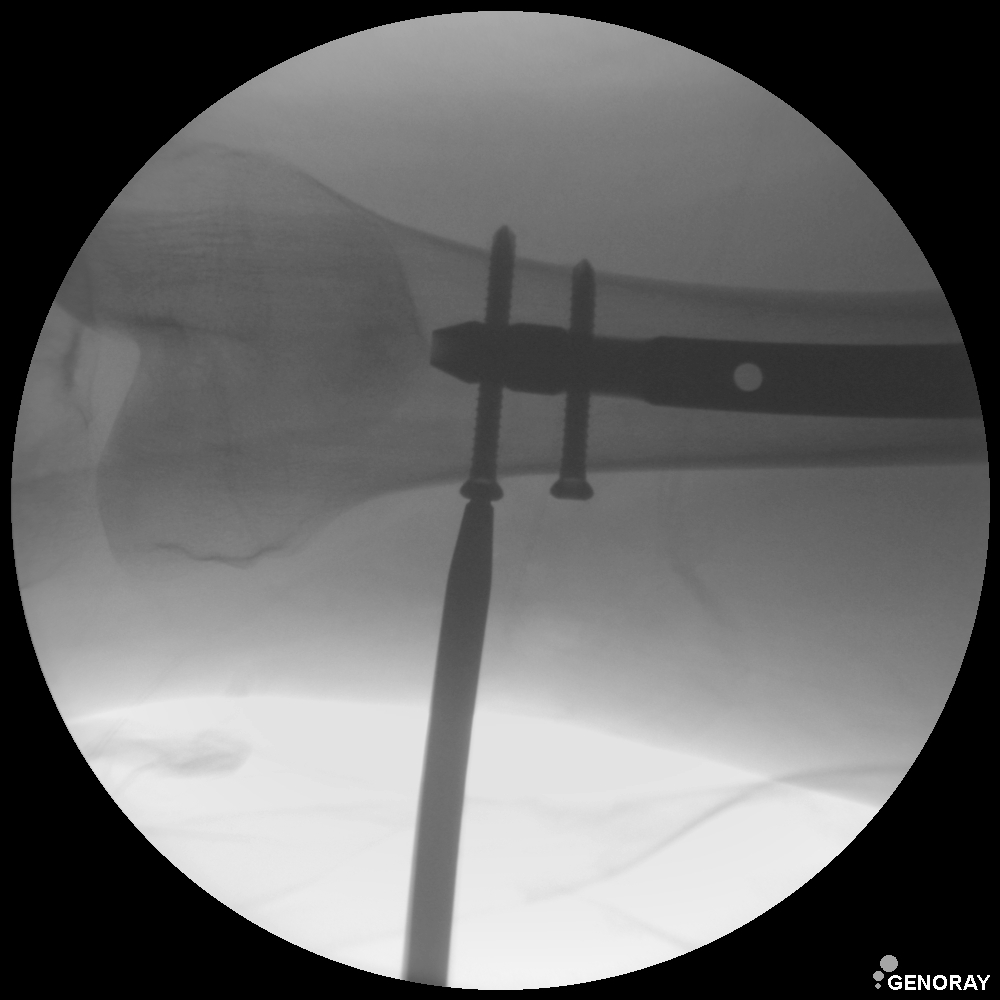

Аппарат применяется в различных областях медицины, таких как хирургия, ортопедия, педиатрия, травматология, урология и многих других. «РЕНЕКС-ОПТИМАЛ» имеет широкий диапазон перемещения и легко позиционируется во всех направлениях.

В качестве приемника используется усилитель рентгеновского изображения (УРИ) с ПЗС-матрицей 1024х1024 пикселей. Мощность рентгеновского питающего устройства 5,3 кВт. Система принудительного воздушного охлаждения, позволяет эффективно использовать аппарат на протяжении долгого времени без перегрева. Широкий диапазон регулирования количества импульсов при импульсной рентгеноскопии позволяет значительно снизить лучшею нагрузку, при этом при необходимости возможно проводить исследования с частотой до 30 кадров в секунду. С-дуга оснащена интерактивной сенсорной панелью управления всеми параметрами исследования на штативе аппарата.

- Непрерывная и импульсная рентгеноскопия с цифровой обработкой изображения.